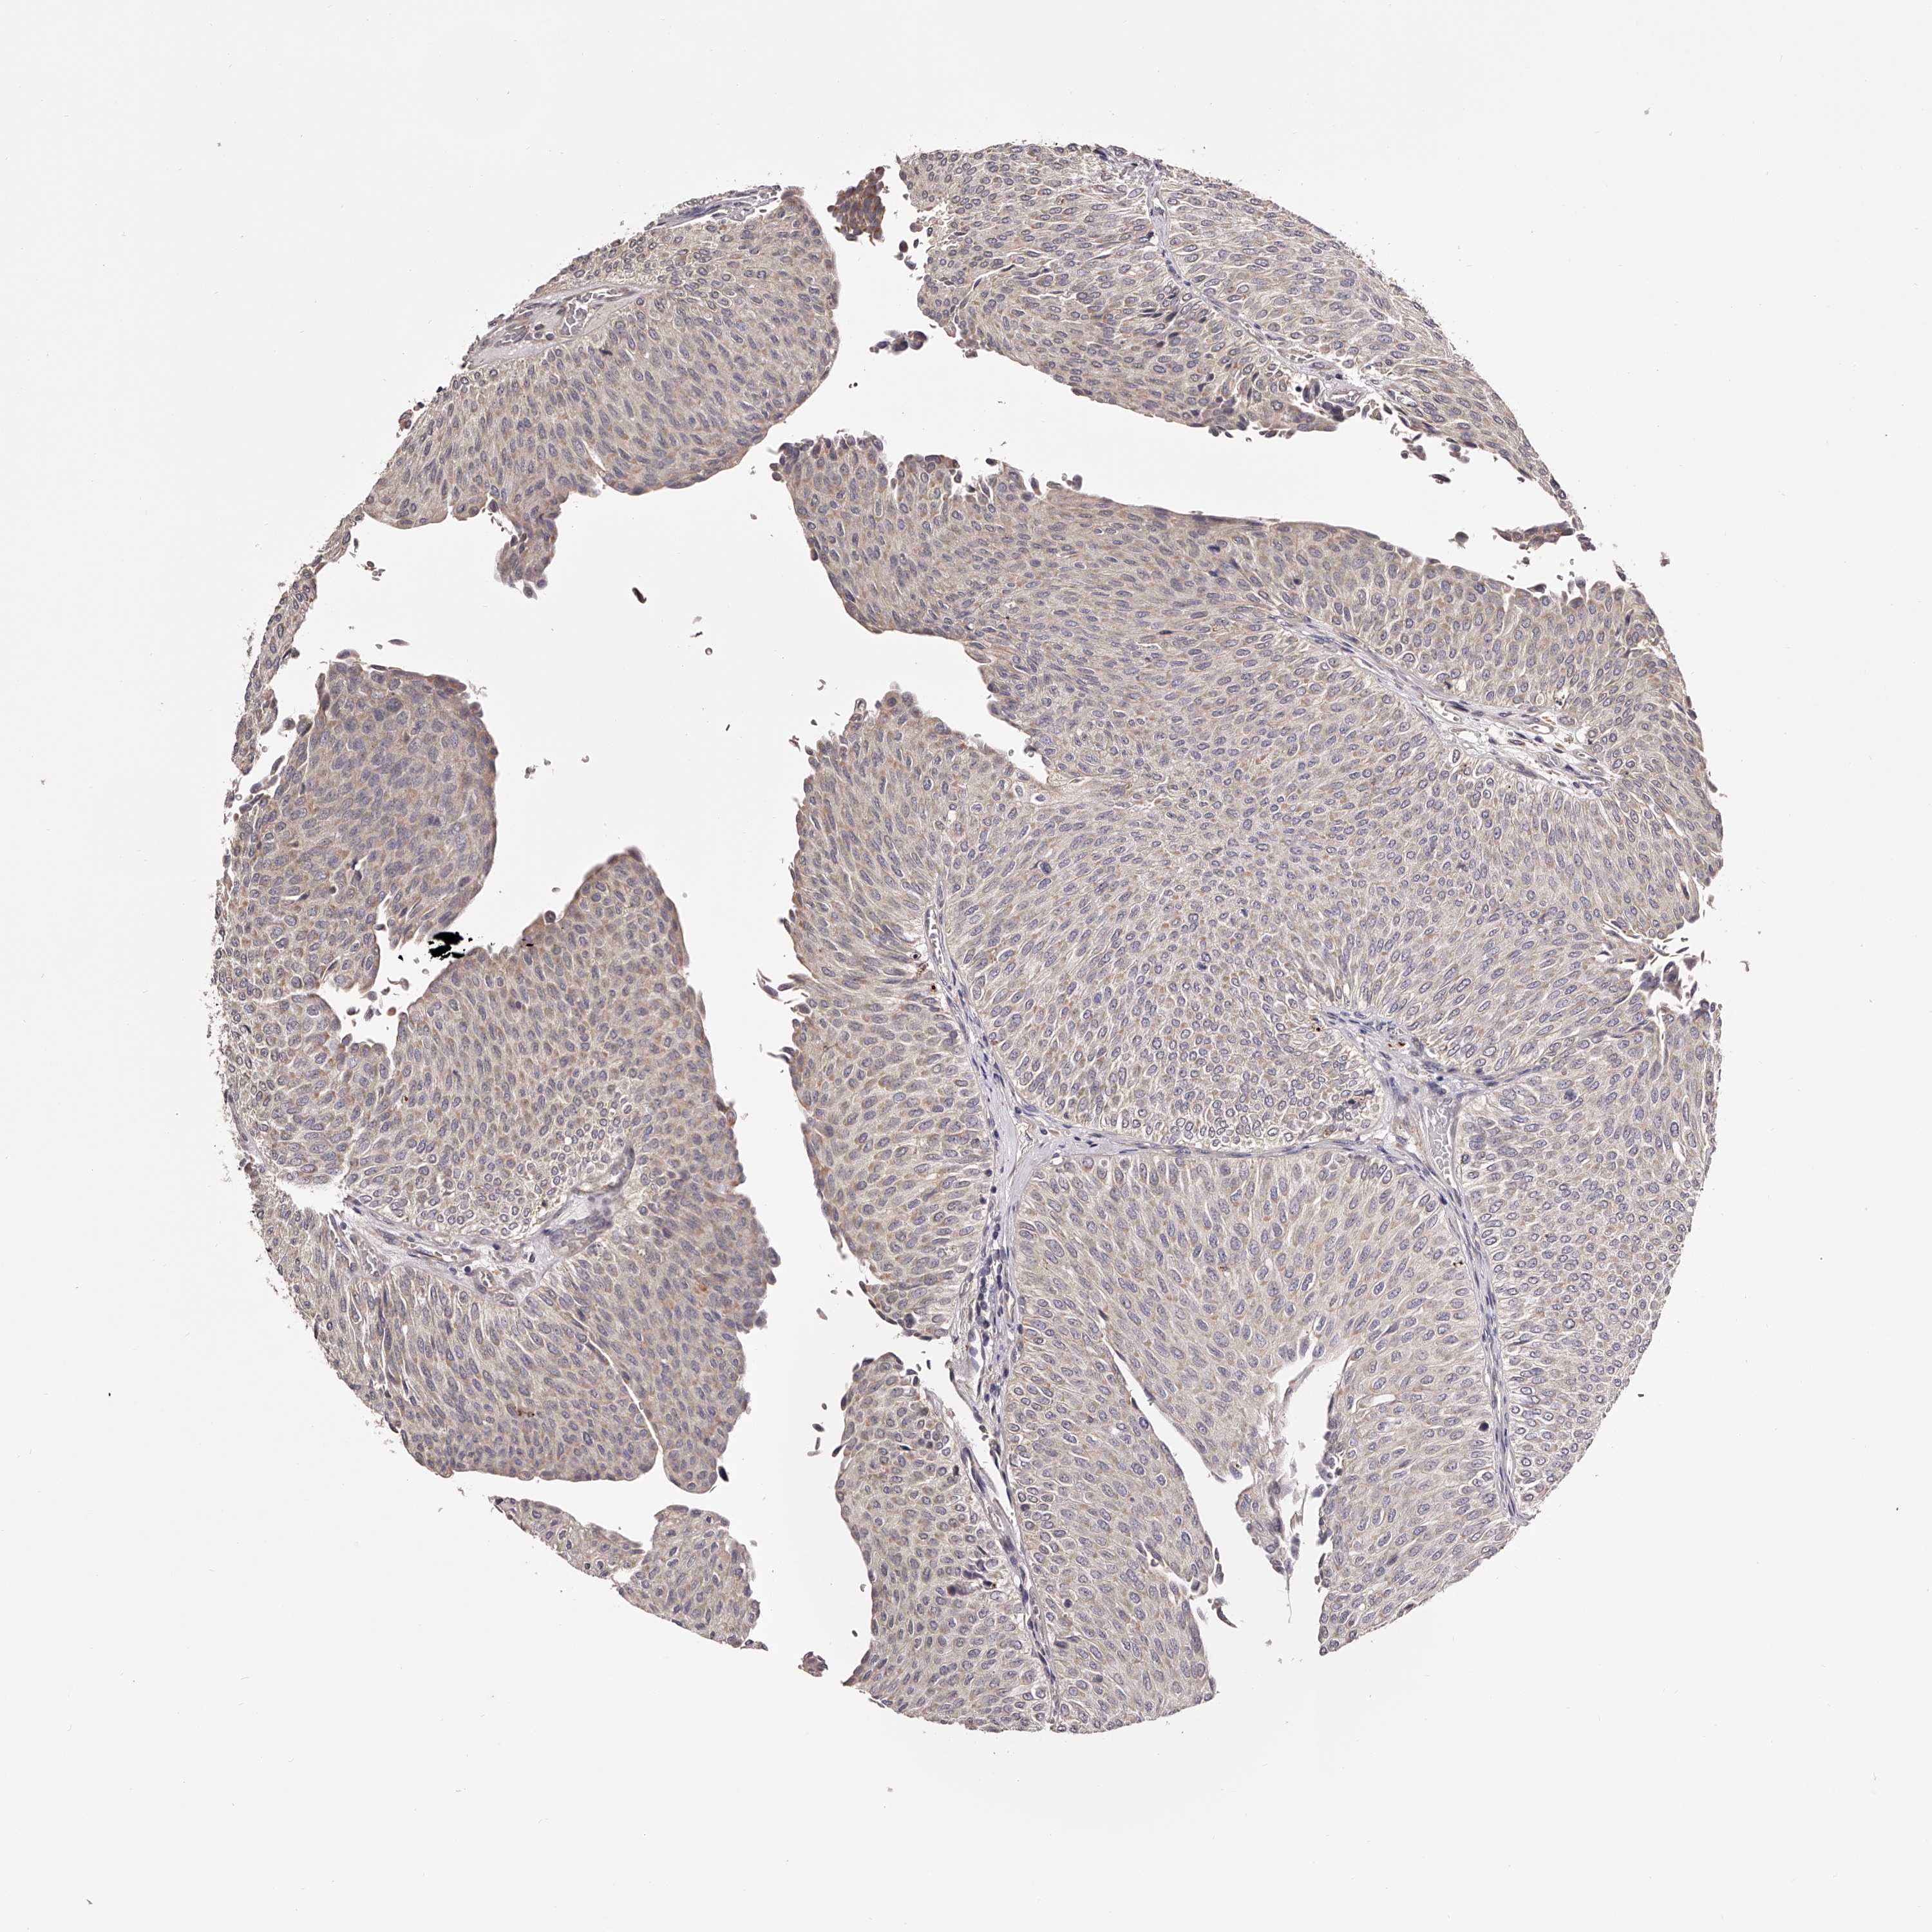

UROTHELIAL CANCER - Protein expressioni

A mouse-over function shows sample information and annotation data. Click on an image to view it in a full screen mode. Samples can be filtered based on level of antibody staining by selecting one or several of the following categories: high, medium, low and not detected. The assay and annotation is described here.

Note that samples used for immunohistochemistry by the Human Protein Atlas do not correspond to samples in the TCGA dataset.

Antibody stainingi

Antibody staining in the annotated cell types in the current human tissue is reported as not detected, low, medium, or high, based on conventional immunohistochemistry profiling in selected tissues. This score is based on the combination of the staining intensity and fraction of stained cells.

Each image is clickable and will lead to virtual microscopy that enables deeper exploration of all samples and also displays staining intensity scores, fraction scores and subcellular localization as well as patient and tissue information for each sample.

Antibody HPA028020

Antibody HPA028095

Antibody HPA028333

Urothelial carcinoma, Low grade

Urothelial carcinoma, High grade